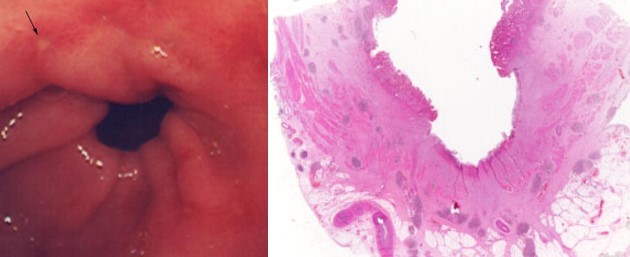

What is this?

SCC of oesophagus